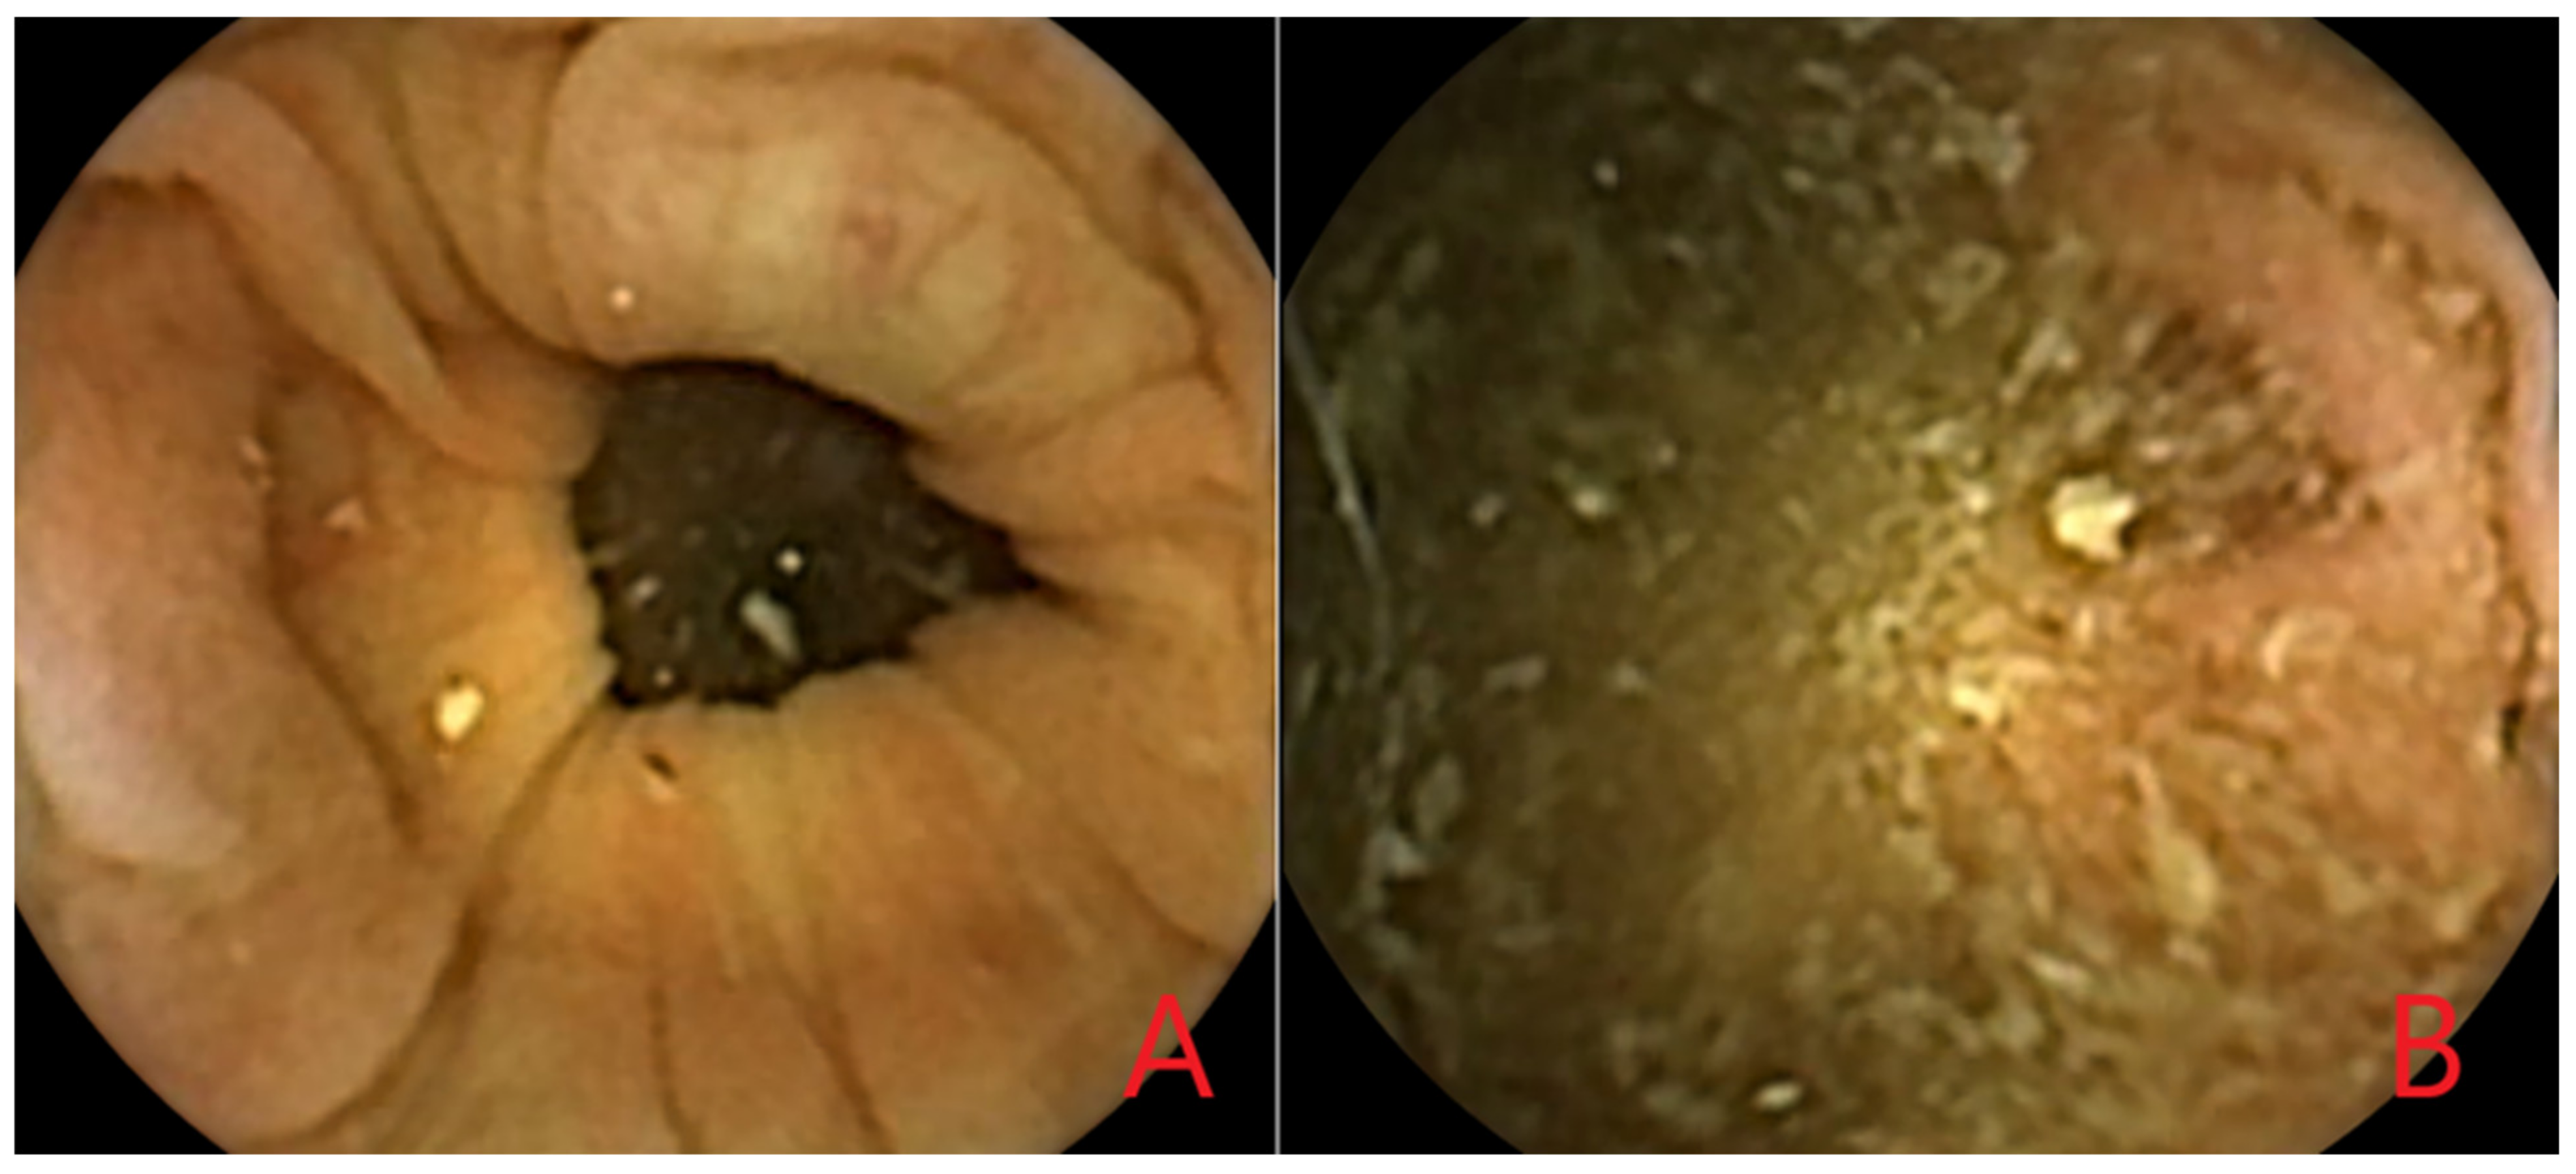

3.5. Artificial Intelligence for Polyp Detection in CCE-2

3.5.1. Development of the Proposed AI Models for Polyp Detection

3.5.2. Performance of the Proposed AI models for Polyp Detection